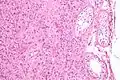

تتميز الخلايا البينية بنواة حمضية، فاتحة اللون، مكورة ودائرية. يحيط بها سيتوبلازم مليء بالشبكات الإندوبلازمية الملساء والميتوكوندريا. وبكميات أقل يوجد في السيتوبلازما ايضاً فجوات دهنية وكريستالات.[2]